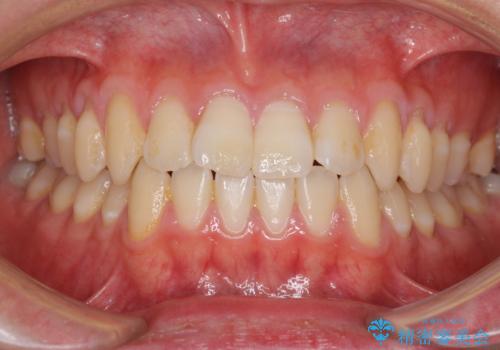

- 上下前歯のデコボコを気にして来院された患者様です。

叢生は軽微であり、費用を抑えて期間もあまりかけずに治療をしたいとのことで、インビザライン・ライトを用いて矯正治療を行うこととしました。